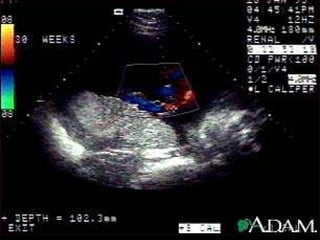

Trocas materno-ovulares Circulação úteroplacentária ; o débito sanguíneo placentário materno = 500ml/min. Circulação fetoplacentária ; o sangue do coração esquerdo fetal    Aorta    art. Umbilicais (baixo teor de O2)    placa corial, chegando aos troncos coriais  1 º , 2 º , 3 º  ordem até os capilares das vilosidades. O retorno do sangue, rico em O2, segue o trajeto das vênulas, troncos 3 º , 2 º  , 1 º  ordem    placa corial até chegar a veia umbilical, desembocando no coração direito.

Trocas materno-ovulares Circulaçãoúteroplacentária ; o débito sanguíneo placentário materno = 500ml/min. Circulação fetoplacentária ; o sangue do coração esquerdo fetal  Aorta  art. Umbilicais (baixo teor de O2)  placa corial, chegando aos troncos coriais 1 º , 2 º , 3 º ordem até os capilares das vilosidades. O retorno do sangue, rico em O2, segue o trajeto das vênulas, troncos 3 º , 2 º , 1 º ordem  placa corial até chegar a veia umbilical, desembocando no coração direito.